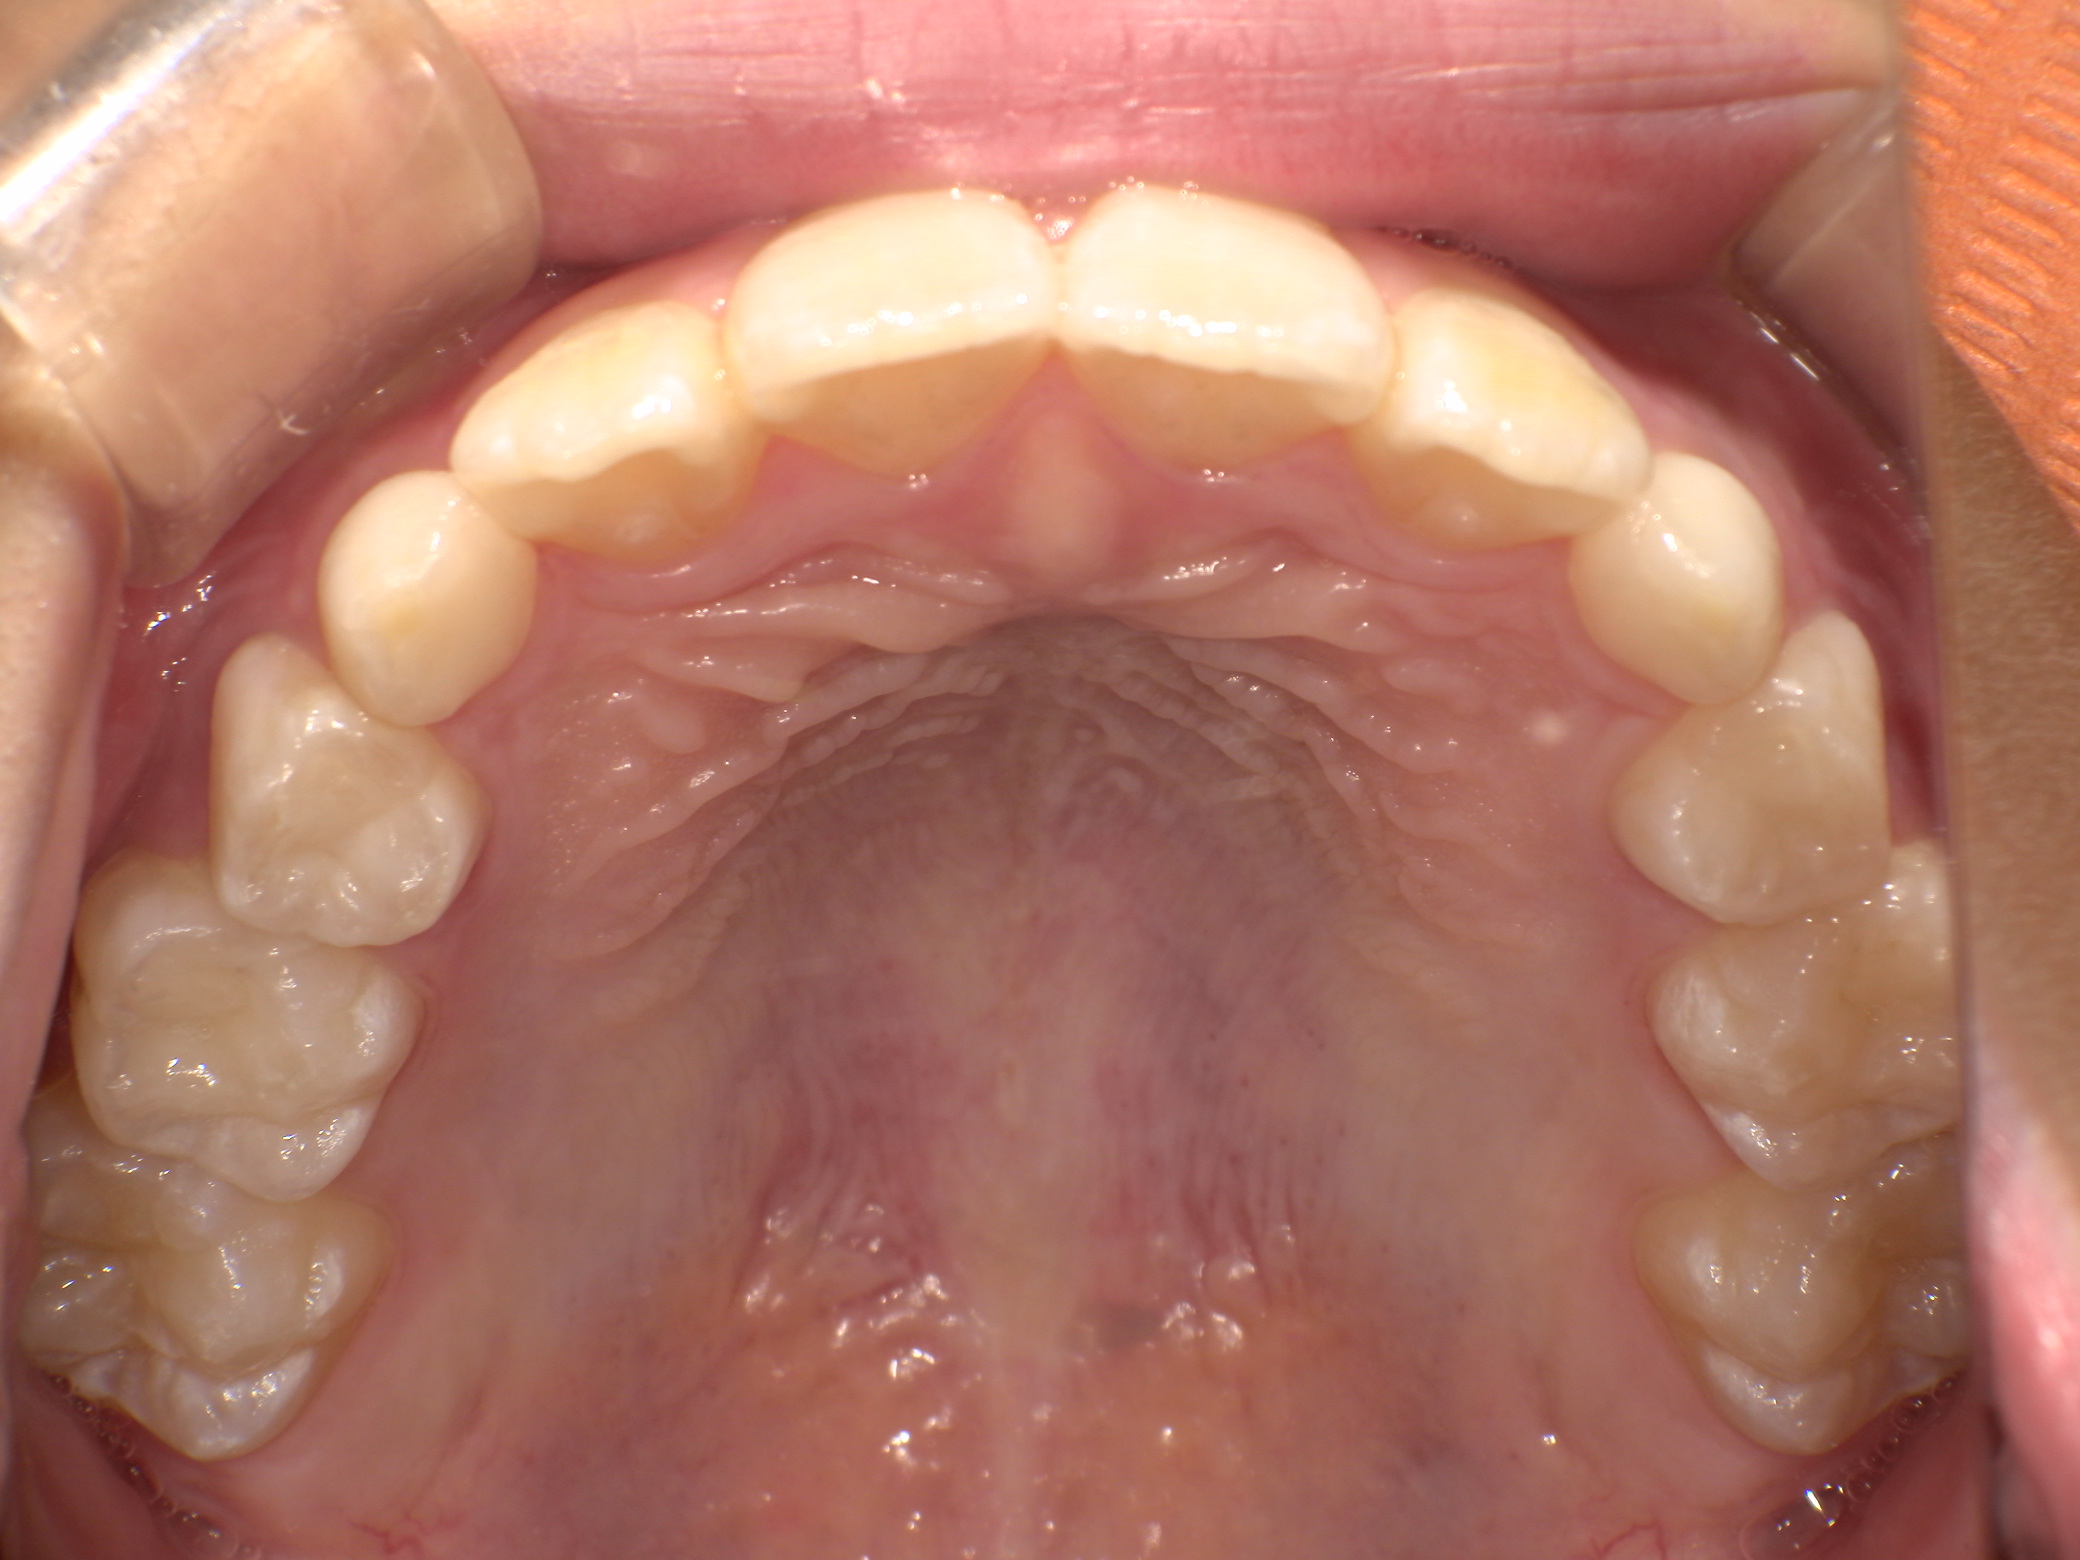

| 年齢・性別 | 8歳3ヶ月の男児 |

|---|---|

| 主訴 | 上顎前歯の位置異常に不安を抱え、歯並びと将来的な咬合状態を整える目的で来院された患者様です。 特に左側の前歯(中切歯および側切歯)の萌出が確認できないことがきっかけとなりました。 |

| 治療期間・回数 | 約5年10ヶ月 |

| 費用 | 460,000円(税別) |